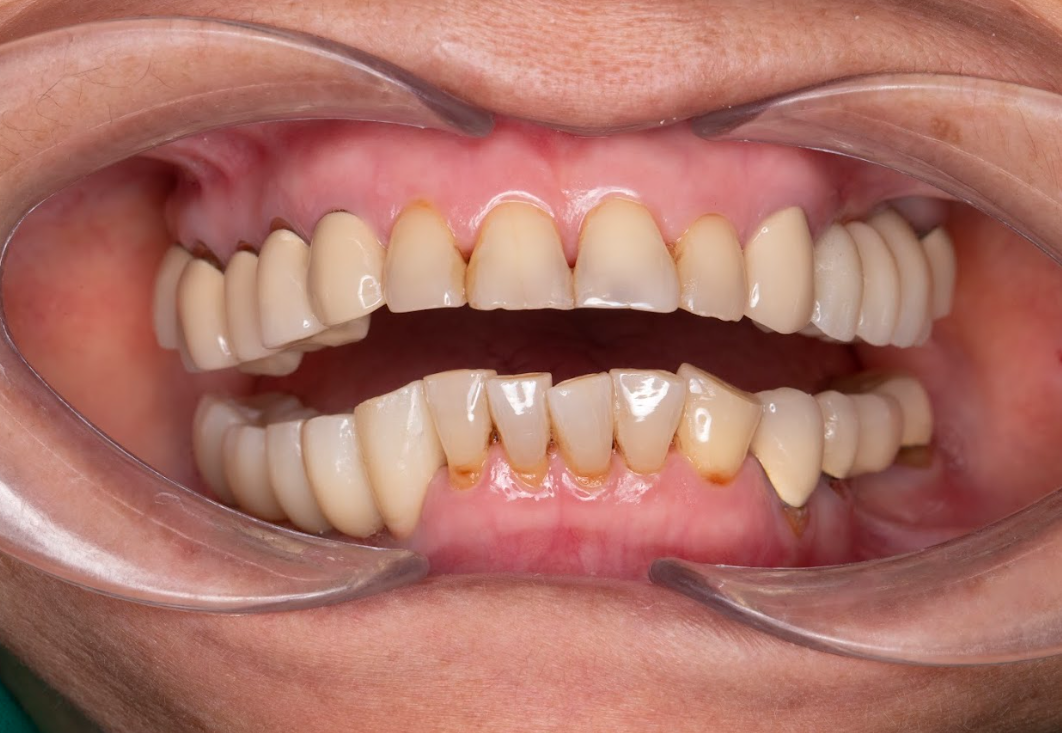

Kết quả sau điều trị

Sau ca điều trị, cô Phương xúc động chia sẻ:

✨ “Tôi không ngờ sau hơn 10 năm, mình lại có thể ăn nhai ngon lành và cười thoải mái như vậy. Cảm giác thật sự như được sống lại tuổi trẻ.”

Kết quả đạt được:

Khôi phục 100% khả năng ăn nhai.

Nụ cười thẩm mỹ, trẻ trung hơn ít nhất 10 tuổi.

Tự tin giao tiếp, cải thiện chất lượng cuộc sống.

Sức khỏe tổng thể tốt lên do ăn uống thoải mái hơn.